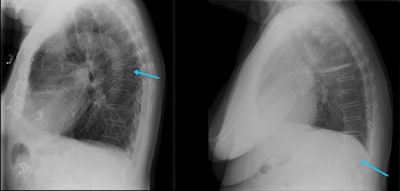

Several factors contribute to underdiagnosis following imaging, including the failure of radiologists to consistently review spinal components of imaging, lack of awareness of the importance of early diagnosis of VFFs and use of ambiguous reporting terminology (e.g., "loss of height" or "wedging"), immature or underdeveloped departmental RIS and alert processes inhibiting rapid dissemination of reports, and inadequate onward referral systems (in particular fracture liaison services), they wrote.

- Implement a policy of automatic sagittal spinal reformatting and display and storage on PACS for cross-sectional imaging studies that include the spine.

- Implement a policy for standardized use of terminology for VFFs -- using the term "vertebral fracture."